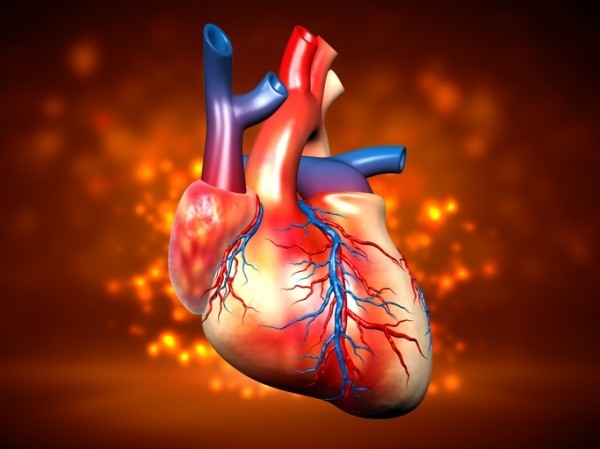

오늘은 정말 많은 분들이 놓치기 쉬운 **치명적인 심장 질환, ‘심근경색’**에 대해 이야기해보려 합니다.심근경색은 말 그대로 심장 근육이 괴사하는 질환으로, 골든타임을 놓치면 생명을 잃을 수 있는 응급상황입니다.

하지만 오늘 알려드린 초기증상 10가지를 잘 알고 있다면, 여러분이나 소중한 가족의 생명을 구할 수 있습니다.심장은 단 한 번의 기회로 살아남기도, 무너질 수도 있는 장기입니다.